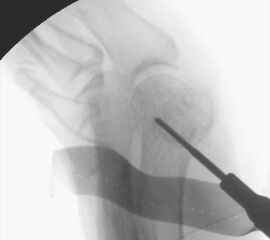

Zum Lesen der Bildbeschreibung und zur Vollansicht bitte die Bilder anklicken.

• Positionierung des Bildwandlers: 90° Winkel zum Os metatarsale I. Benötigt wird die Durchleuchtung des Vorfußes a.p., seitlich und schräg.

Operationstechnik

Der von Isham/Reverdin beschriebenen minimal invasiven Technik zur Korrektur einer Hallux valgus Deformität liegen 4 Operationsschritte zu Grunde:

2. Subcapitale intraartikuläre Osteotomie

3. Laterales Release

Die Folge der Operationsschritte sollte strikt von 1. - 4. erfolgen, da ansonsten die mediale Closing Wedge Osteotomie bei vorzeitigem lateralem Release und/oder Akin Osteotomie nicht geschlossen werden kann. Nach der von Isham beschriebenen Originaltechnik finden Implantate keine Anwendung, zur Sicherung und besseren Fixation können osteosynthetische Verfahren angewandt werden (siehe auch Fehler, Gefahren und Komplikationen).